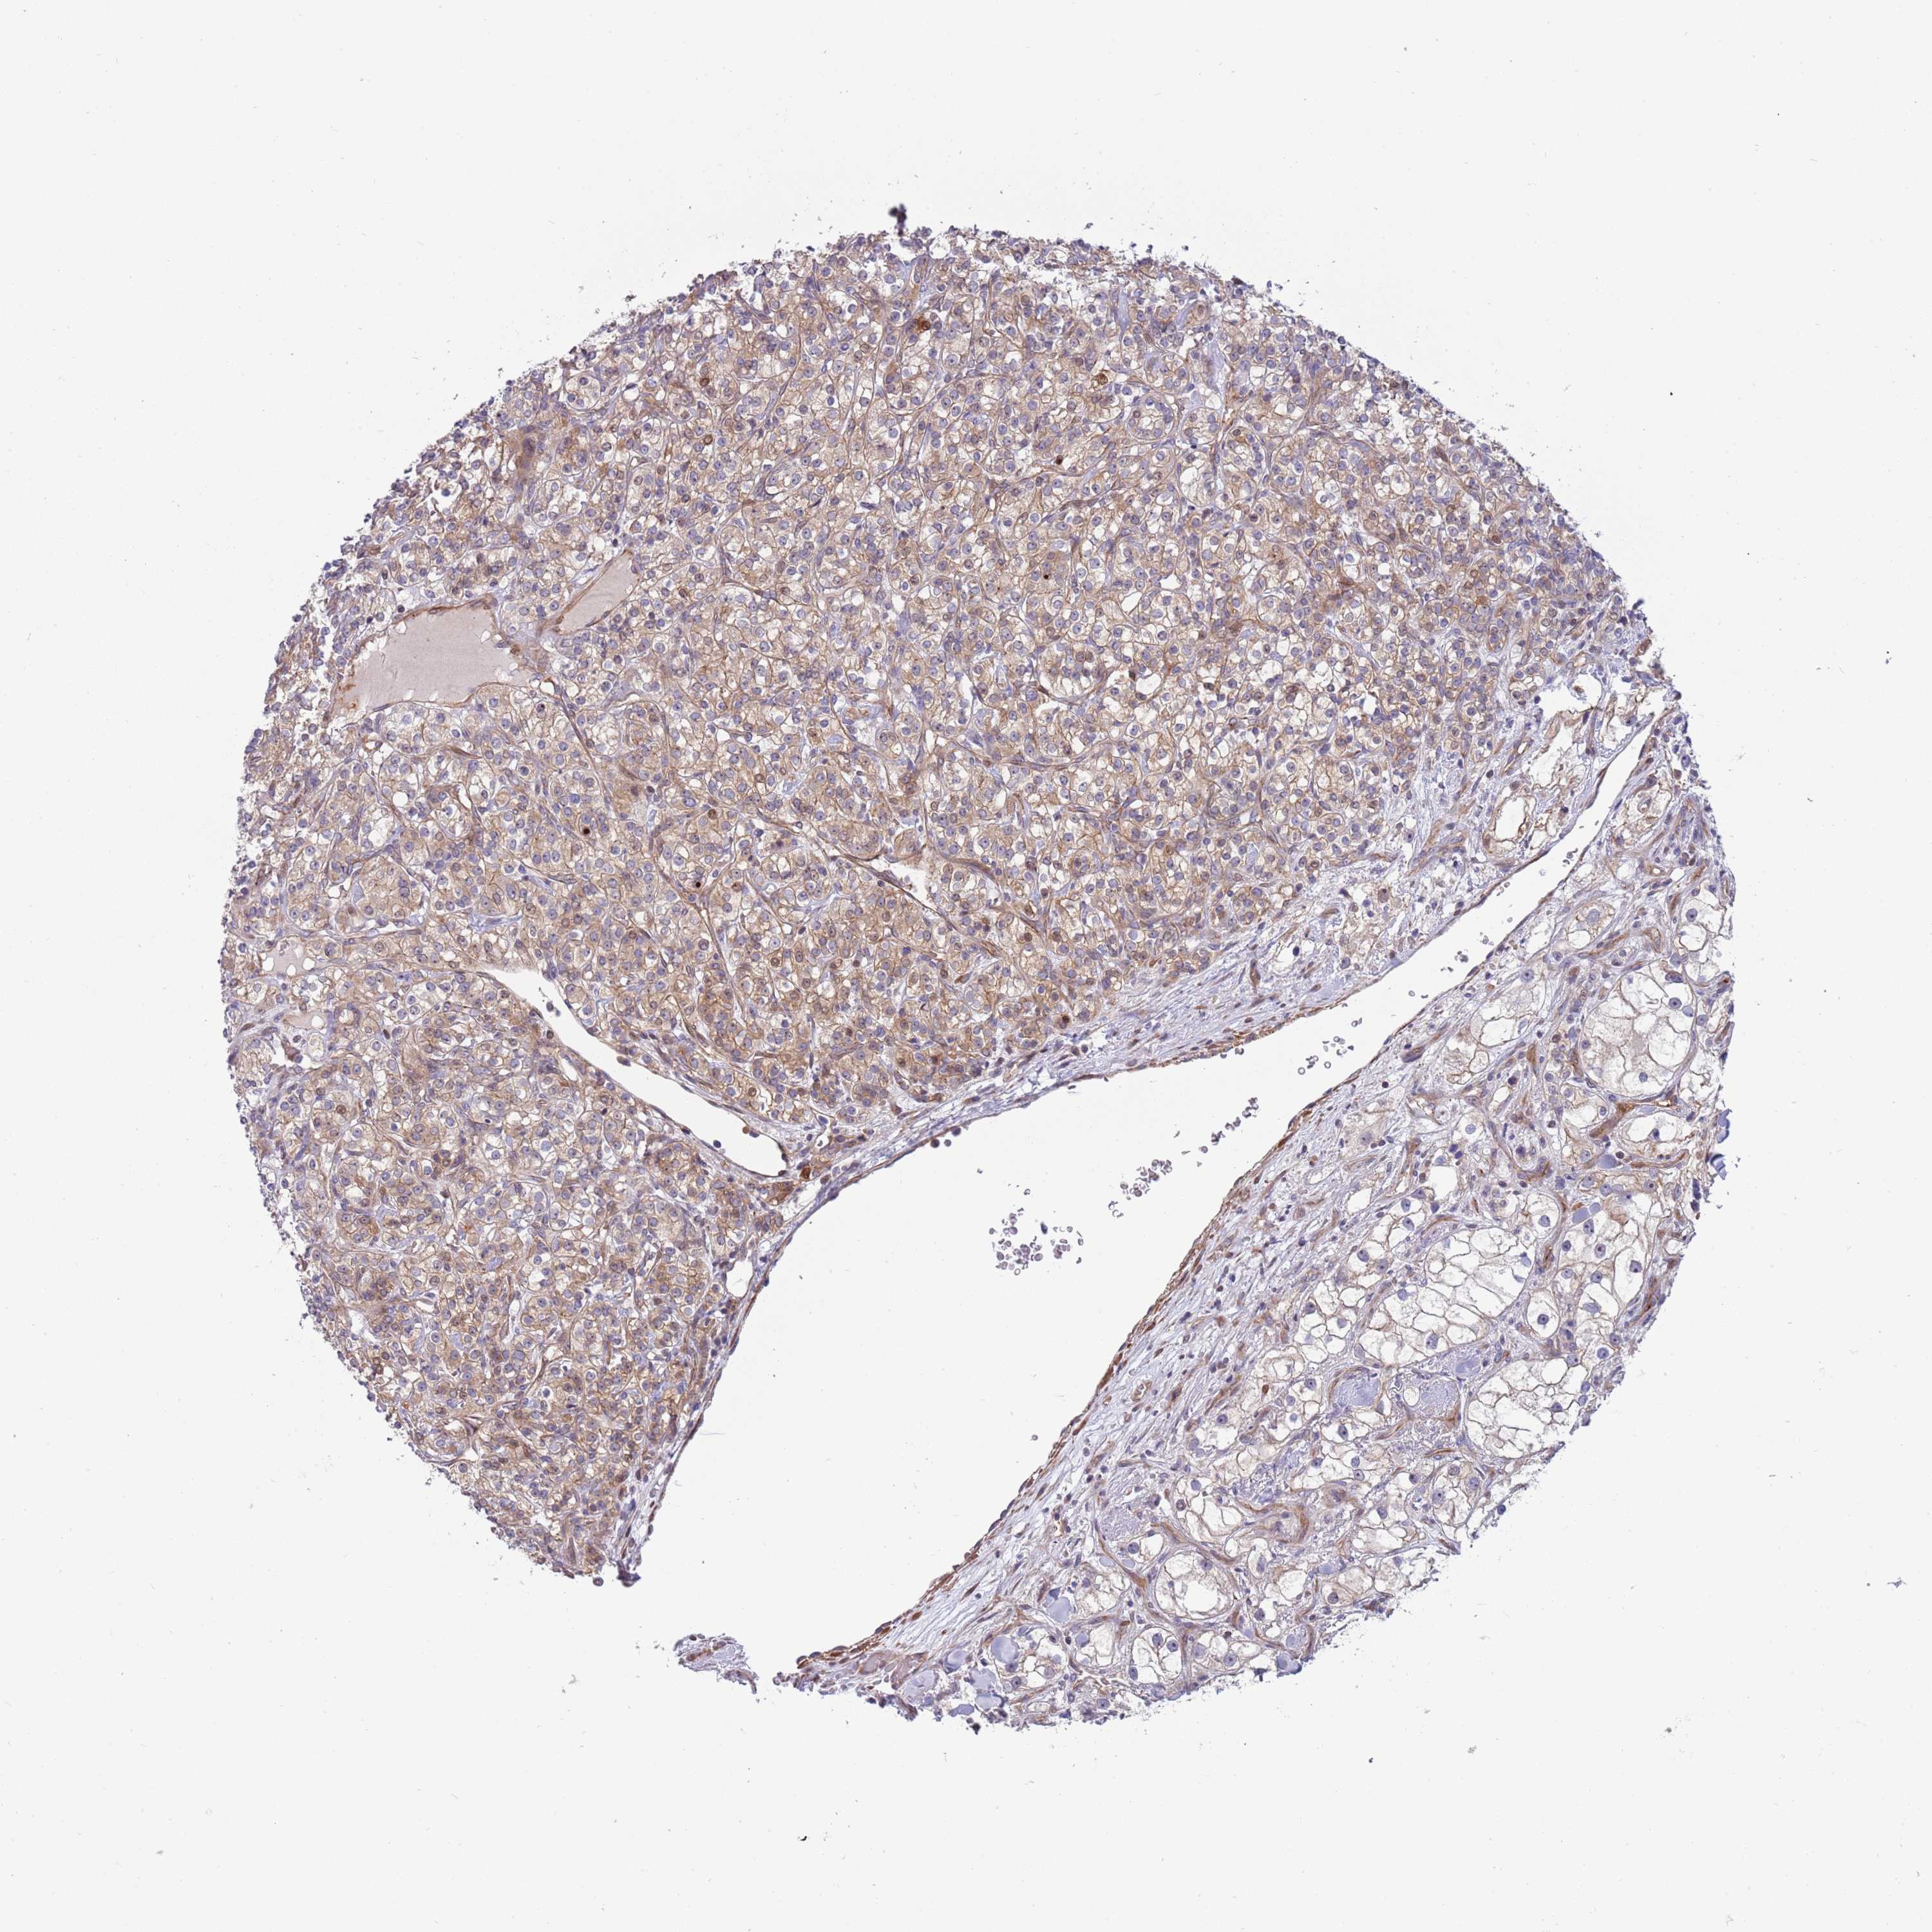

KIDNEY RENAL CLEAR CELL CARCINOMA (TCGA) - Interactive survival scatter ploti

The Survival Scatter plot shows the clinical status (i.e. dead or alive) for all individuals in the patient cohort, based on the same data that underlies the corresponding Kaplan-Meier plots. Patients that are alive at last time for follow-up are shown in blue and patients who have died during the study are shown in red.

The x-axis shows the expression levels (FPKM) of the investigated gene in the tumor tissue at the time of diagnosis. The y-axis shows the follow-up time after diagnosis (years). Both axes are complimented with kernel density curves demonstrating the data density over the axes. The top density plot shows the expression levels (FPKM) distribution among dead (red) and alive patients (blue). The right density plot shows the data density of the survived years of dead patients with high and low expression levels respectively, stratified using the cutoff indicated by the vertical dashed line through the Survival Scatter plot. This cutoff is automatically defined based on the FPKM cutoff that minimizes the p-score. The cutoff can be changed by dragging the vertical line or by entering a cutoff value in the square labeled "Current cut-off".

Under the Survival Scatter plot the p-score landscape (black curve; left axis) is shown together with dead median separation (red curve; right axis). Dead median separation is the difference in median mRNA expression between patients who have died with high and low expression, respectively. It is calculated as follows: median FPKM expression of dead patients with high expression - median FPKM expression of dead patients with low expression. This is intended to aid the user in visually exploring custom cutoffs and the associated p-scores and dead median separation.

Individual patient data is displayed and can be filtered by clicking on one or more of the category buttons on the top of the page. Categories describing expression level and patient information include: high, low, alive, dead, female, male and tumor stages. The scale of the x-axis can be toggled between linear and log-scale by clicking on the "x log" button. Mouse-over function shows TCGA ID, patient information and mRNA expression (FPKM) for each patient.

& Survival analysisi

Kaplan-Meier plots summarize results from analysis of correlation between mRNA expression level and patient survival. Patients were divided based on level of expression into one of the two groups "low" (under cut off) or "high" (over cut off). X-axis shows time for survival (years) and y-axis shows the probability of survival, where 1.0 corresponds to 100 percent.

ITGB6 is not prognostic in Kidney Renal Clear Cell Carcinoma (TCGA)

Best expression cut offi

Based on the FPKM value of each gene, patients were classified into two groups and association between prognosis (survival) and gene expression (FPKM) was examined. The best expression cut-off refers the FPKM value that yields maximal difference with regard to survival between the two groups at the lowest log-rank P-value. Best expression cut-off was selected based on survival analysis .

When clicking on this number, the vertical dashed line indicating cut-off, the interactive survival plot, and the Kaplan-Meier curve will be adjusted to show results based on the best expression cut-off.

: 4.71

P scorei

Log-rank P value for Kaplan-Meier plot showing results from analysis of correlation between mRNA expression level and patient survival.

N/A

TCGA RNA samplesi

RNA-seq data is reported as average FPKM (number Fragments Per Kilobase of exon per Million reads), generated by the The Cancer Genome Atlas (TCGA) .

Normal distribution across the dataset is visualized with box plots, shown as median and 25th and 75th percentiles. Points are displayed as outliers if they are above or below 1.5 times the interquartile range. FPKM values of the individual samples are presented next to the box plot.

Average pTPM 7.1

Number of samples 521